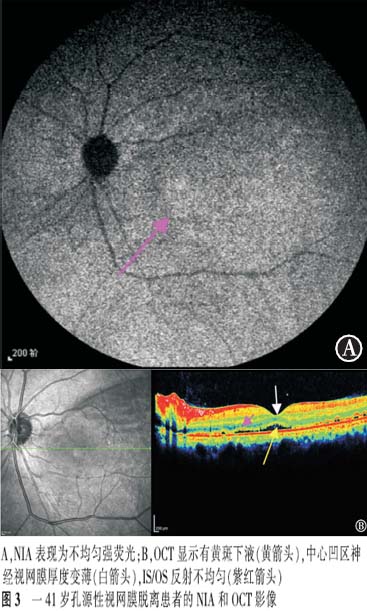

【摘要】 目的 近红外眼底自发荧光检查(NIA)联合OCT对孔源性视网膜脱离巩膜扣带术后早期黄斑结构的评估价值。方法 前瞻性系列病例研究。对21例(21眼)伴黄斑脱离的孔源性视网膜脱离患者行巩膜扣带术,于术后3个月行NIA及OCT检查。观察检查图像的异常和手术后视力的恢复情况。对视力的变化进行配对t检验,NIA与术后BCVA的相关性采用双向无序分类变量资料的关联性进行分析。结果 NIA:16眼表现为弱荧光周围围绕着强荧光,5眼表现为不均匀的强荧光。OCT:20眼存在黄斑下液;中心凹视网膜神经纤维层的厚度6眼变薄,14眼正常,1眼增厚;21眼IS/OS反射异常。视力恢复情况:术后3个月与术后1 d比较,NIA表现为弱荧光周围围绕着强荧光者,视力差异有统计学意义(t=9.922,P<0.05),NIA表现为不均匀强荧光者,视力差异无统计学意义(t=2.409,P>0.05),黄斑NIA表现与术后BCVA变化高度相关(C=0.502,P<0.05)。结论 孔源性视网膜脱离巩膜扣带术后早期,黄斑结构与功能均尚未完全恢复,需要我们加以重视。

【Abstract】 Objective To evaluate the changes in macular structure in the early stages after undergoing scleral buckling surgery for rhegmatogenous retinal detachment (RRD); to use melanin-related near-infrared fundus autofluorescence (NIA) combined with optical coherence tomography (OCT) for studing the changes. Methods This was a prospective case-series study. Melanin-related near-infrared fundus autofluorescence (NIA) and optical coherence tomography (OCT) examinations were performed on 21 patients with local primary RRD three months after undergoing a successful scleral buckling procedure for retinal reattachment. The RRDs in all 21 eyes involved the macula. To check the anomalies fo the images and the recovery of the vision after surgery. Changes invision after surgery were compared with a paired t test. The correlation of NIA and BCVA was analyzed with the relevance of two-way disorderly classification variable data. Results NIA revealed that 16 eyes had hypofluorescence surrounded by hyperfluorescence and 5 eyes had uneven hyperfluorescence. Submacular fluid was found in 20 eyes. The retinal nerve fiber layer in the central fovea became thinner in 6 eyes. In one eye, the retinal nerve fiber layer in the central fovea became thicker, and in another 14 eyes the thickness of the retinal nerve fiber layer was normal. The reflection from the photoreceptor inner and outer segment junction (IS/OS) was abnormal in all 21 eyes. Visual acuity measured with NIA revealed that the hypofluorescence which was surrounded by hyperfluorescence had improved at the 3-month follow-up compared to the 1-day follow-up examination (t=9.922, P<0.05), while VA measured at the same time revealed that uneven hyperfluorescence had not improved at the 3-month follow-up (t=2.409, P>0.05). The macular NIA results and the change in postoperative BCVA were highly correlated (r=0.502, P<0.05). Conclusion Macular function and structure do not fully recover in the early stages after undergoing scleral buckling to treat RRD. More attention should be paid to this problem.